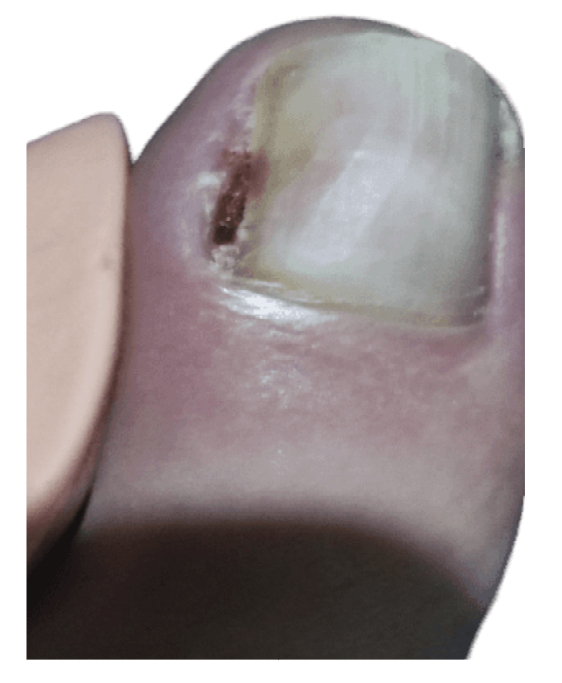

Tras empeoramiento del cuadro clínico, el 14 de noviembre de 2022 se realiza en su centro de salud la retirada parcial de la placa ungueal lateral del pie izquierdo junto con raspado, retirando tejido hiperqueratósico y de granulación. El procedimiento es repetido 48 h más tarde (16 de noviembre de 2022) por no haber retirado toda la lesión (Figura 3), cambiando el tratamiento antibiótico a anaclosil 500 mg 1/6 h y posteriormente a ciprofloxacino 500 mg 1/12 h durante las siguientes semanas.

Figura 3. Semana 8. Resección parcial de tejido hiperplásico realizado en su centro de salud.

La paciente presenta inicialmente mejoría del dolor, aunque nunca termina de ceder completamente (Figura 4). Refiere recurrencia de la lesión ungueal lo que le lleva a consultar una segunda opinión a las 6 semanas de la intervención con otro podólogo. Este último con fecha 27 de diciembre (Figura 5) realiza cultivo bacteriano de la lesión, resultando negativo, y también valoración de la lesión mediante ecografía (sin informe). El 13 de enero la paciente es intervenida quirúrgicamente mediante técnica fenol-alcohol en el borde lateral del primer dedo del pie izquierdo (Figura 6).

Figura 4. Semanas 9-14. Recurrencia progresiva de la lesión tras resección parcial.